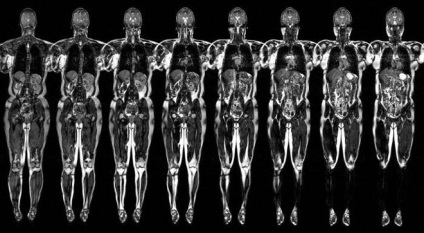

Az orvostudományban, nincs sok eljárások teljes bizalommal lehet nevezni teljesen biztonságos az emberre. Ezek közé tartozik az MRI és vizsgálata a belső szerveket. Ellentétben röntgen diagnosztika, mágneses rezonancia megengedett a betegek számára minden életkorban, beleértve a gyermekeket és a terhes nők. Ez a módszer a diagnózis - az egyik legjobb, hogy tanulmányozza az egész test egy eljárásban. Ez különösen nagyra értékelik abban az esetben, ha a szükséges teljes körű onkopoisk az ellenőrzés az összes belső szervek, szövetek és rendszerek.

Hogy van a diagnózis

Vizsgálata az egész test MRI elég gyors - 30-60 percig, attól függően, hogy a kutatási célokat. Például onkopoisk tovább tart, mint a hagyományos komplex MRI, mint egy orvos szükség részletesebb képet egy vékony „szelet” a belső szerveket.

Beteg a ruhát egy könnyű anyagból ing, és tegye az asztalra szkenner. Karja és lába rögzített hevedereket. Ugyanezt lehet tenni a fej, ha egy személy nehéz tartani, hogy hosszú ideig ugyanabban a helyzetben. Ha az orvos által felírt egy MRI kontraszt, az injekciót vénába a könyök néhány percig a vizsgálat előtt.

Ezután az orvos kimegy a szobából a telepítést, és magában foglalja a szkennert. A táblázat a páciens található a rajta hengerelt egy gyűrűt szkenner és hajt végre több hosszanti «gördülési». A telepítés után a munka a vizsgázó lehet azonnal tegye a ruháját, és menjen haza. Az eredmények egy átfogó diagnózis ismert lesz a néhány óra, maximum egy nap. Ők részt vettek a megfejtése az orvos radiológus. Néha keskeny szakemberek vesznek részt ebben a folyamatban.